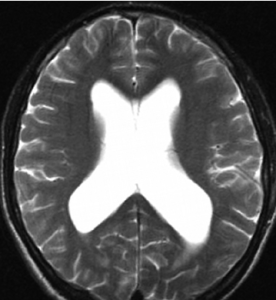

交通性腦積水交通性腦積水另一較為特徵性的表現為腦溝變淺、變平,但灰白質界限仍清楚,常可據此幫助作出診斷。但有時交通性腦積水亦可同時發生腦溝、腦池擴大,特別是側裂池、基底池和小腦橋腦池,這種情況多見於基底池等有關腦池的炎症或腫瘤所致的部分腦脊液循環通路受阻,以及蛛網膜顆粒的吸收功能障礙。

上述交通性腦積水的徵象較為典型,但有時不全部出現,造成診斷困難,Gado等提出了一種評分方法,側腦室擴大分為輕度(+1)、中度(+2)、和重度(+3);第三腦室正常(0)或擴大(+2),腦溝正常或擴大(-2)。如果分數相加大於等於3,提示交通性腦積水。

CT和MRI所見腦室普遍擴大而腦溝正常或消失是交通性腦積水的典型表現,尤其是第四腦室擴大時,更易作出診斷。但有時交通性腦積水錶現不典型,特別是合併腦萎縮時,診斷較為困難,必要時可結合病史、腰穿腦脊液滴注試驗和腦脊液壓力測定來確診。